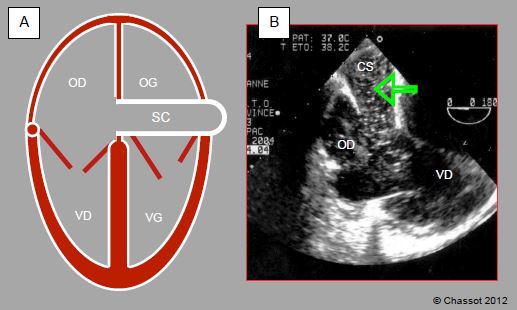

- 14.6.2 Repères anatomiques